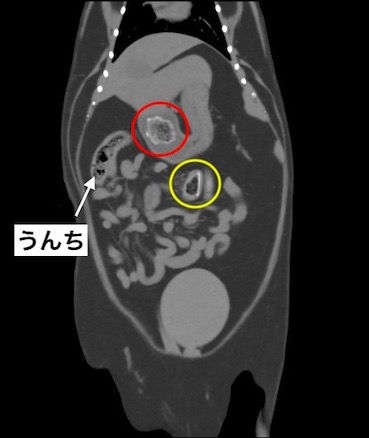

CT検査所見です。

診断:十二指腸内異物による腸閉塞(黄色丸)、および胃内異物(赤丸)